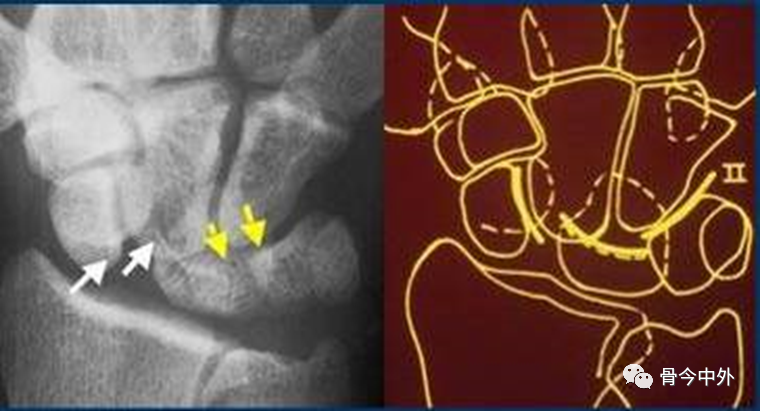

图17

腕骨弧线中断;弧线中断提示骨折或韧带断裂导致的半脱位或脱位。上图显示弧线Ⅰ在月骨-三角骨关节处的中断。

图18

弧线Ⅱ 中断于舟月关节和月骨-三角骨关节(上图)。弧线Ⅰ虽有缺口但仍呈光滑弧线,可认为是完整的。